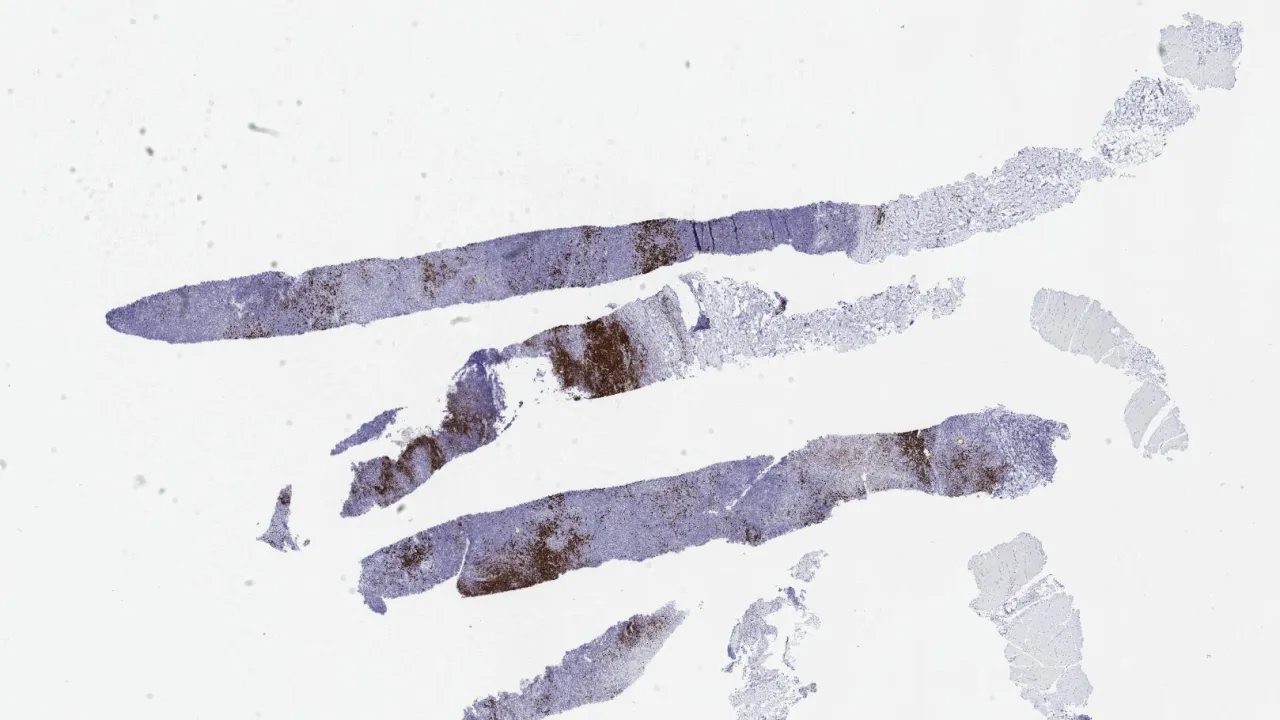

Soft Tissue, Subcutaneous panniculitis-like T-cell lymphoma, TCR beta stain